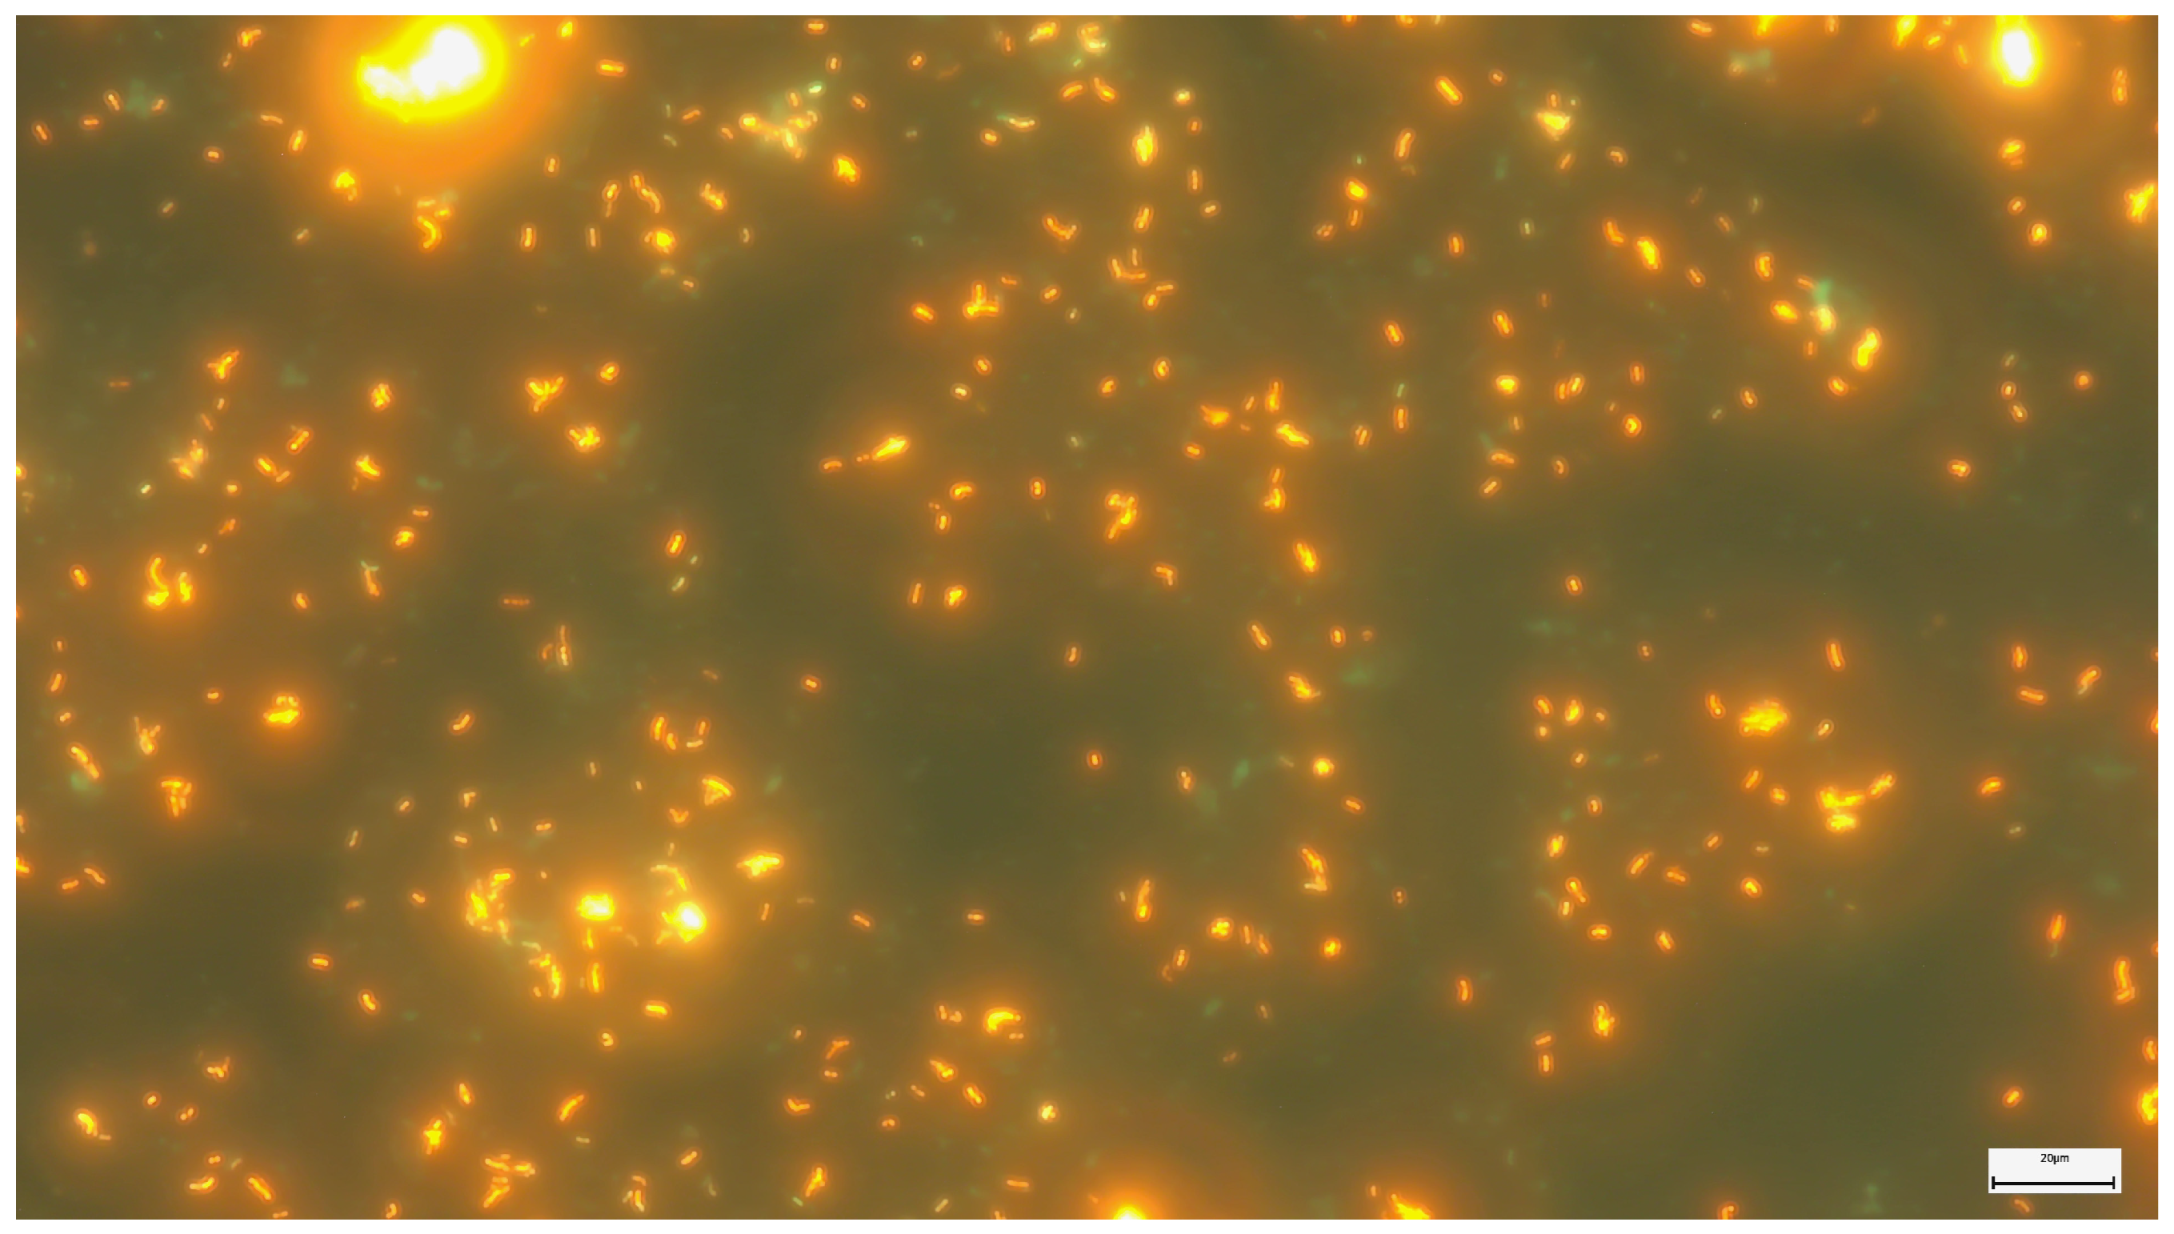

2.2. Microscopic Examination with Fluorescent Staining

2.3. The Fluorescent Microscopy Method with Electroluminescent Diodes (LEDs)

2.5. USP Method (Modified Auramine–Rhodamine Ziehl–Neelsen)